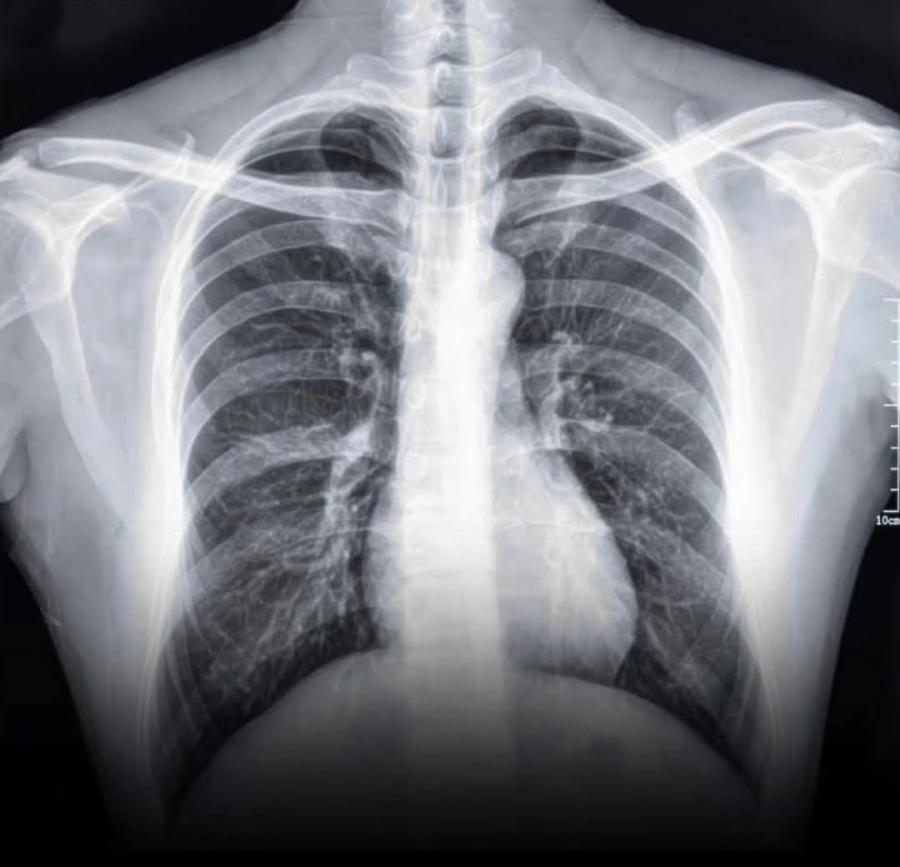

شاهد ماذا فعلت السيجارة الإلكترونية برئة فتى أردني .. صورة

وجّهت طبيبة أردنية تحذيرًا شديد اللهجة إلى الأهالي والمراهقين من مخاطر استخدام أجهزة التدخين الإلكتروني "Vape"، وذلك بعد أن نشرت صورة صادمة تُظهر رئة متليّفة لشاب يبلغ من العمر 16 عامًا، تعرّض لمضاعفات خطيرة بعد عام واحد فقط من استخدام هذه الأجهزة بشكل سري.

وقالت الطبيبة في منشورها: "هاي صورة رئة شاب عمره 16 سنة، كان يستخدم الـVape من ورا أهله.. سنة وحدة بس، كانت كافية تتسبّب بتليّف دائم في الرئة. اليوم، عايش على الأوكسجين ليل نهار، بياخد الاسطوانة معاه على المدرسة، وممنوع يلعب رياضة أو يعيش حياته طبيعي."

وأشارت إلى أن الحالة الطبية التي أصيب بها المراهق تُعرف علميًا باسم "Popcorn Lung" أو Bronchiolitis Obliterans، وهي حالة مرضية نادرة ولكنها خطيرة، تُسبب تلفًا دائمًا في الشعب الهوائية الدقيقة داخل الرئة، ولا يوجد لها علاج يعيد الرئة إلى حالتها الطبيعية.